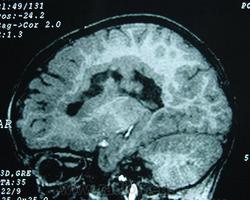

Гетеротопии. Перивентрикулярная гетеротопия. Субэпендимальная нодулярная (узелковая) гетеротопия.

Наиболее частым вариантом миграционных нарушений является гетеротопия - скопление нейронов, остановившихся в различных аномальных местах на пути следования к коре головного мозга. Такая остановка происходит не позже 5-го месяца внутриутробного развития. Изолированный участок узловатой массы называется «гетеротопион». В настоящее время описаны следующие варианты гетеротопии:

- субэпендимальная нодулярная (узелковая) гетеротопия;

Перивентрикулярная субэпендимальная гетеротопия